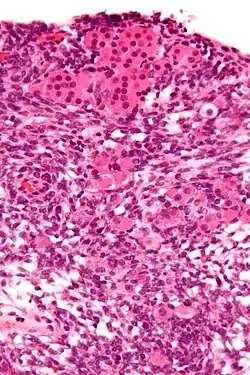

| Micrograph of a Sertoli–Leydig cell tumour. The Leydig cells have abundant eosinophilic or light pink cytoplasm. The Sertoli cells have a pale/clear cytoplasm. H&E stain. | |